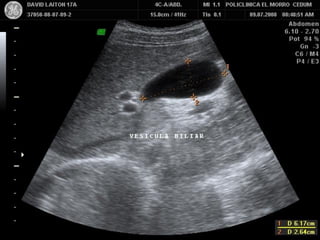

VESICULA BILIAR

• Visible

• Fundus variable

• Cuello Fijo

•

-

Visible

Fundus variable

Cuello Fijo

Forma y tamaño variable

Longitudinal de 7 a 10 cm

Transverso hasta 3,9 cm